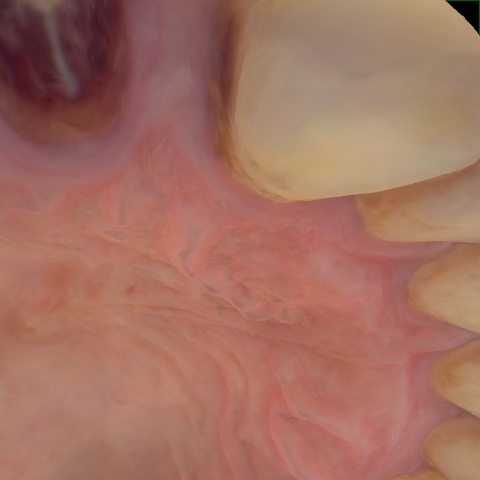

Annotated as "Good"